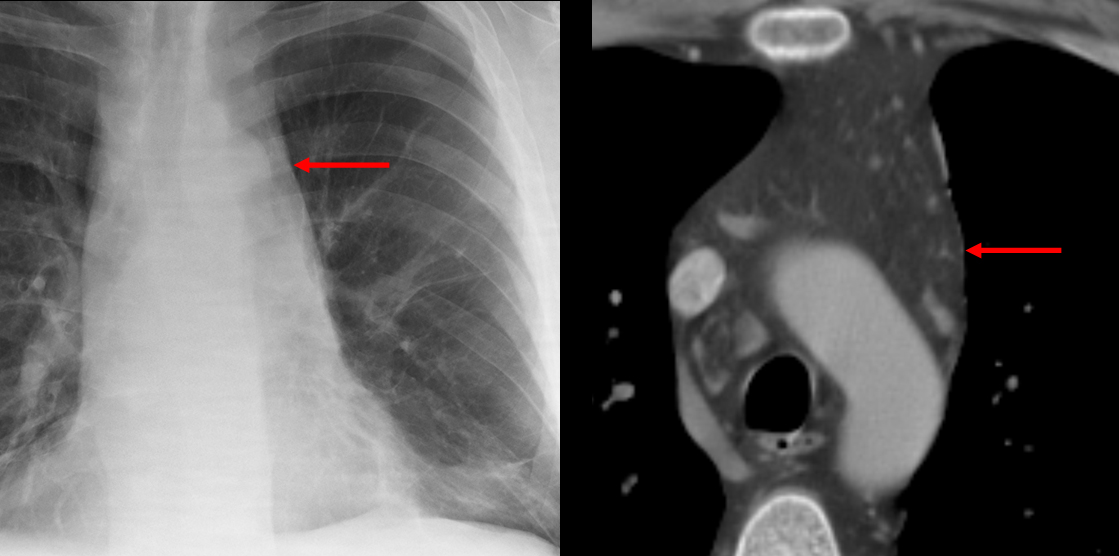

Gallery Mediastinum Miscellaneous mediastinal fat

mediastinal fat